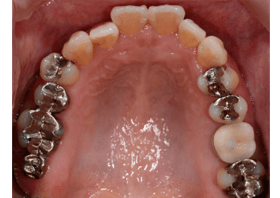

Before

ホワイトニングの後、オールセラミッククラウン、セレックを用いた男性の場合

| 治療内容 | ホワイトニング治療後にオールセラミッククラウンとセレックによる審美治療を行いました。 |

| 治療期間・回数 | 1.5ヶ月・7回 |

| 治療費用 | 390,000円(税込) |